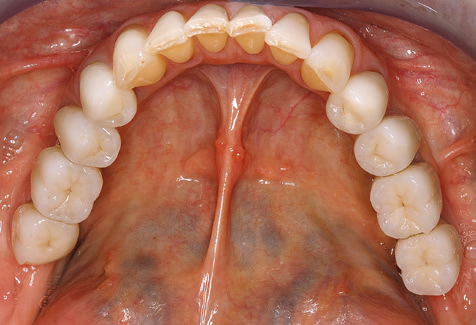

A 52-year-old patient presented in our clinic for the first time in 2004 following tooth loss in the third quadrant, expressing a desire for a new prosthetic restoration. Periodontal and radiological diagnostics revealed the need for extensive periodontological treatment. In addition, teeth 48, 28 and 27 were attributed a very poor prognosis and were subsequently extracted (Fig. 1). Following the successfully completed, systematic periodontological treatment, a fixed dental implant was inserted with the introduction of five implants in tooth regions 35, 36, 37, 46 and 47. Prosthetic treatment of the natural teeth was effected with veneered zirconium dioxide ceramic crowns; the implants were composed of two-piece, individual zirconium dioxide abutments and similarly veneered crowns made of a zirconium dioxide ceramic (Cercon base colored, Dentsply Sirona Lab). Definitive insertion of the prosthetic restoration occurred in 2005.

Due to the presence of periodontal disease, SPT was performed every three months in the first years following the insertion. The patient demonstrated a high degree of motivation and good compliance. The pocket depths recorded annually revealed a stable periodontal situation with a BOP index of below five per cent. On the basis of the stable periodontal situation and good cooperation on the patient’s part, the recall interval was extended to every six months as of the sixth year of the prosthetic function phase. Following the change in the recall interval, the respective annual documentation of the periodontal status continued to reveal a stable periodontal situation with no increase in the pocket depths and a BOP index below five per cent (Fig. 2a and b).

The ten-year check-up revealed no indications of advancing clinical attachment loss or peri-implant bone substance loss (Fig. 3).

The patient continues to visit the clinic every six months for SIT. In the following, the patient is taken as an example for demonstrating the individual working steps in a structured SPT session as it has been performed with barely any modifications over the last 12 years. Of course, some new materials and devices have been integrated into the concept over the years. This clinical case report presents the current material and device concept.